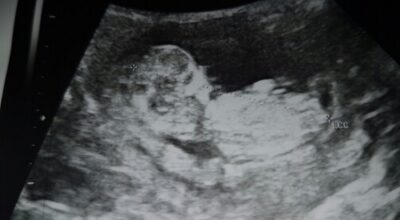

Mi bebe